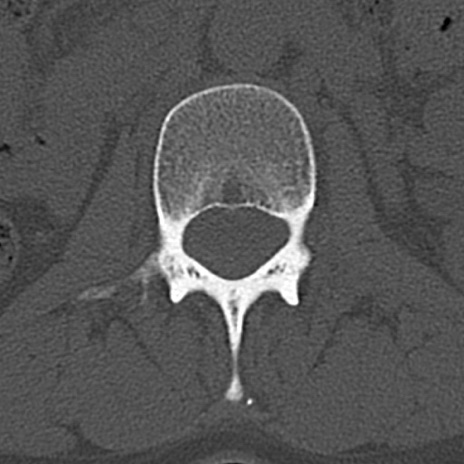

【整形】TIPS症例4 腰椎CT(横断像)

腰椎CT

横断像と矢状断像